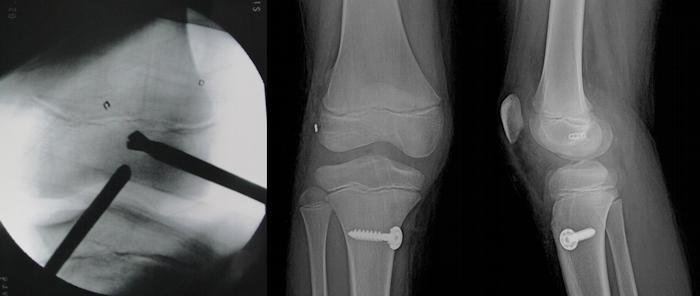

ACL ön çapraz bağ nasıl tedavi edilir?

ACL ön çapraz bağ tedavisi cerrahi müdahalelerle yapılmaktadır. Ön çapraz bağı onararak dizi stabilize eden bu yöntemde yırtılan bağ değiştirilir. Burada önemli olan bir başka husus da rehabilitasyon sürecidir. Hastanın bu süreçte fizik tedavi yöntemleriyle dizinin güçlendirilmesi sağlanır. Doktorun vereceği fizik tedavi programı eklem çevresindeki kasları da harekete geçirir ve yeni bağlar bu programla korunur. Bu konuda alanında uzman kişilerle bu tedavi süreci tamamlanmalıdır. ACL ön çapraz bağ tedavisini sizler için en iyi şekilde uygulayarak bu konudaki başarılarını kanıtlayan hekim kadromuz daima yanınızda.